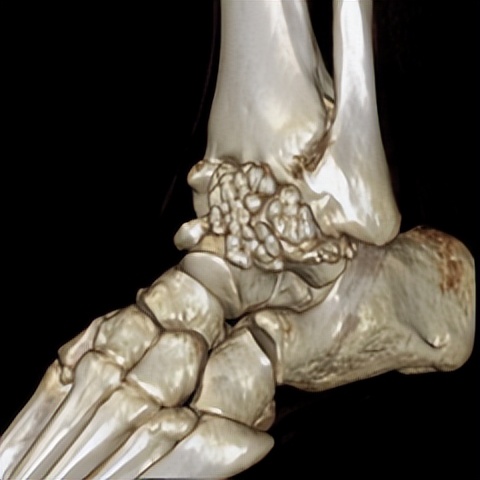

何河北制定了详细的手术方案,为患者开展踝关节镜下滑膜软骨瘤取出术+距腓前韧带重建术。他从患者踝关节中取出32颗“珍珠”(关节游离体),然后进行踝关节外侧韧带重建。

▲术后CT显示滑膜软骨瘤完全取出,韧带重建良好。

据何河北医生介绍,对于踝关节损伤,现在最前沿的方法是踝关节镜下修复或者重建距腓前韧带。该技术为全镜下微创,手术时间短,手术创伤小,术后疼痛感较轻,效果良好。